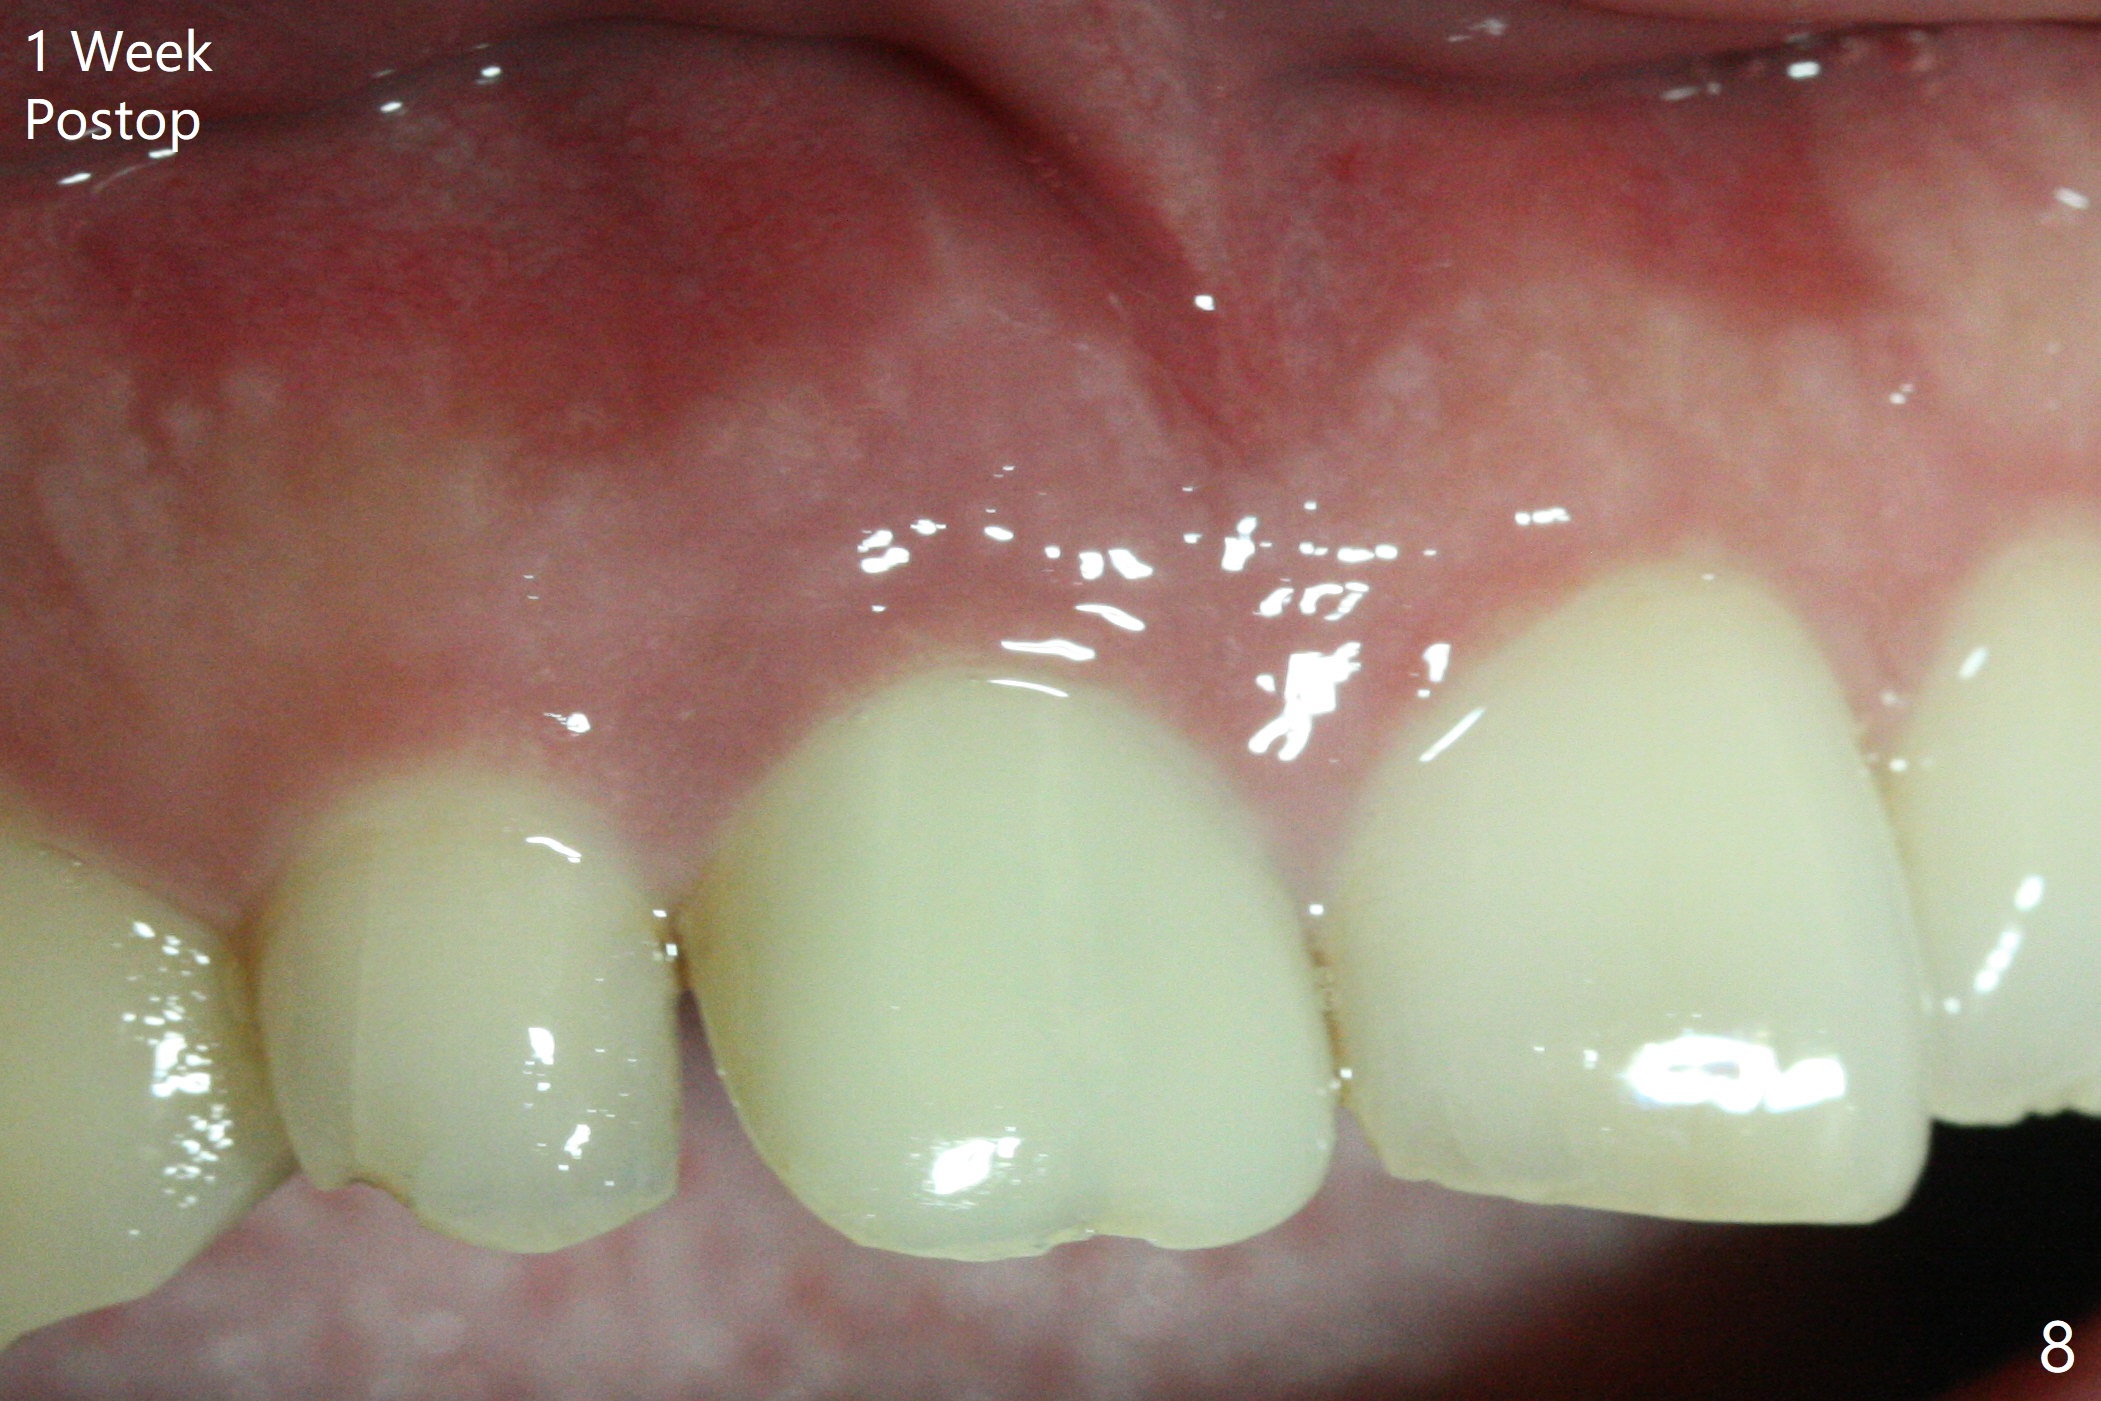

The buccal gingiva at #8 is erythematous (Fig.1: *), which is associated with the tooth fracture line (Fig.2 with granulation tissue: *). The buccal plate remains intact. Osteotomy is initiated in the palatal wall of the socket (Fig.3,4). The initial osteotomy depth is 16 mm (Fig.5); the trajectory is going to be adjusted as shown by arrows. The trajectory improves when a 3.8x15 mm dummy implant is placed (Fig.6). The definitive implant (3.8x16 mm) appears to be placed at an appropriate level (Fig.7). A 4.5x3 mm temporary abutment is inserted for an immediate provisional. As routine, Vera Graft is placed in the buccal gap. The buccal gingival erythema reduces without tenderness 1 week postop (Fig.8). Although the provisional is unstable, there is no bone loss 2 months 20 days postop (Fig.9). Because of the loose provisional (partial detachment from the underlying temporary abutment), impression is taken earlier (3 months postop, Fig.10,11). Due to the pointed abutment tip, the crown is redone 3 times. By the time of cementation (nearly 5 months postop), the socket appears to have healed (Fig.12).